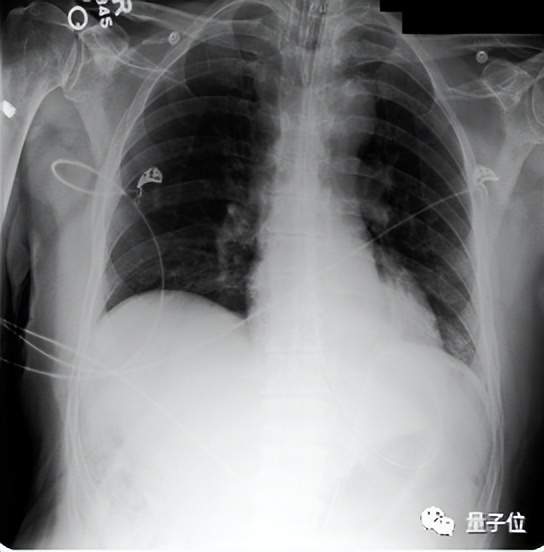

而在246份真实胸部X光片中,临床医生表示,在高达40.50%的病例中,Med-PaLM M生成的报告都要比专业放射科医生的更受采纳,这表明Med-PaLM M并非“纸上谈兵”,用于临床指日可待。

如下图所示的胸部x光解读和皮肤病变分类任务所示,这些指令有一种写提示语的味道,以“你是一个很给力的放射科助理”开头。

(3)零样本思维链推理能力涌现。Med-PaLM M可以通过胸部X射线图像检测没有训练过的结核病,与针对该类数据集进行专门优化过的SOTA结果相比,它的准确率已相差不大。

(4)放射性报告生成测试中,80B参数的Med-PaLM M平均有40.50%的报告比放射科医生做的更好(被临床医生采纳),而12B和562B,分别为34.05%和32.00%。

另外,遗漏和错误率测试显示,Med-PaLM M 12B和84B模型平均每份报告的遗漏率最低,为0.12,其次是562B模型为0.13。这一结果与MIMIC-CXR上人类放射科医生基线报告的相当。